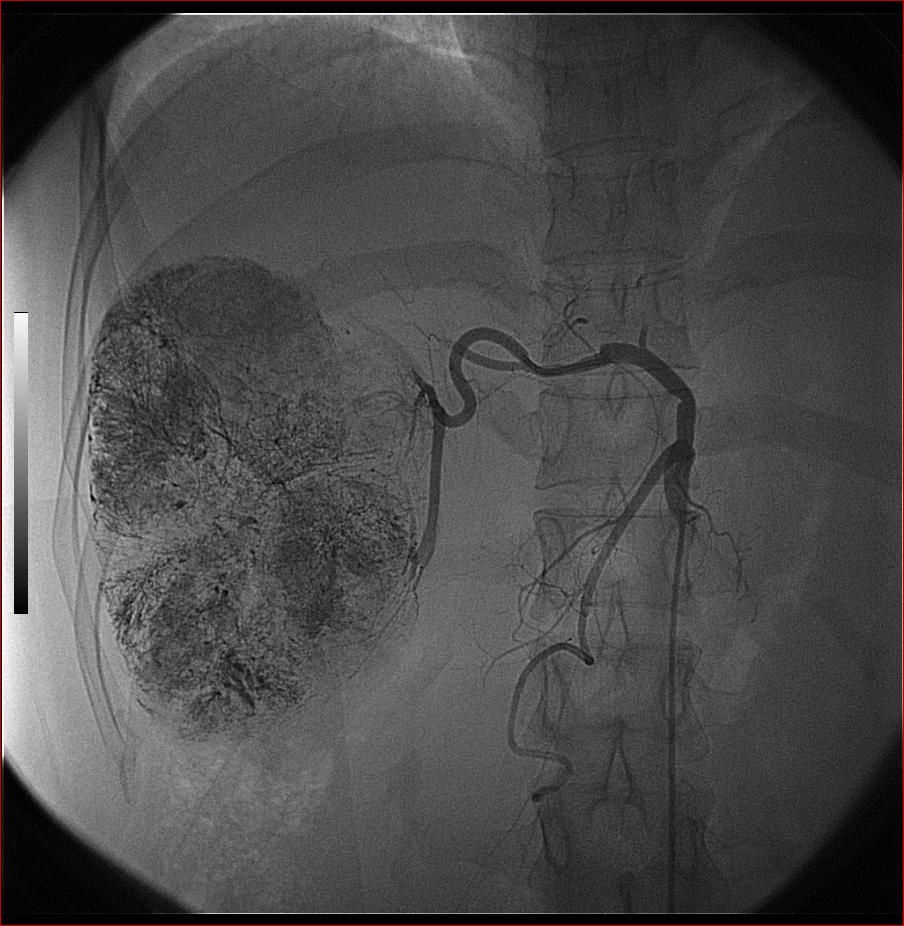

标题: DSA0138:F38Y,肝脏病变

第二次(50天后)

栓塞的非常理想。

好牛的,右肝动脉发自肠系膜上动脉,不用微导管分次进行末梢栓塞,肿瘤染色完整。再次学习了。